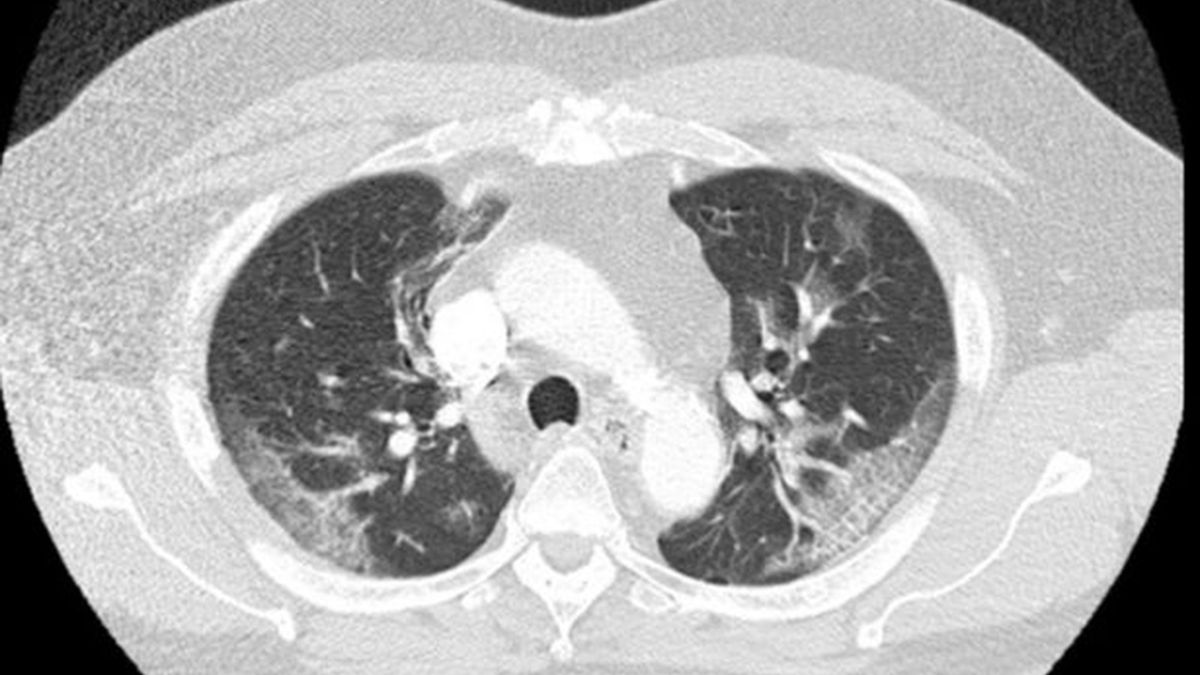

Płuca pacjenta zarażonego koronawirusemPłuca pacjenta zarażonego koronawirusem

Lekarze początkowo nie powiązali objawów z zarażeniem koronawirusem. Jednak wykonane zdjęcia RTG płuc wykazały znaczne zmiany w tym organie. Na tej podstawie zdecydowano o przetestowaniu 62-latka pod kątem koronawirusa. Test pokazał wynik pozytywny.